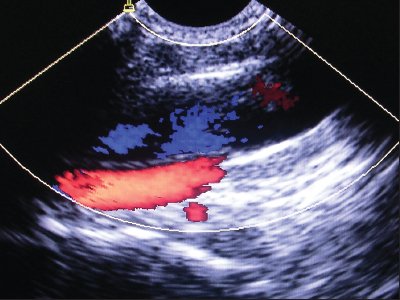

Обследовано более 300 больных детей при катетеризации центральных вен с неотложными состояниями, вызванными инфекционными заболеваниями, в возрасте от 1 мес до 14 лет с массой тела от 2,6 до 62 кг. Для исследования использовались ультразвуковой сканер SonoAce-Pico (фирма "Medison", Южная Корея) с возможностью цветового допплеровского картирования, микроконвексный датчик с изменяемой частотой от 4 до 9 МГц. В своей практике мы применяли статическую и динамическую методики ультразвукового наведения.

Статическая методика: контрольное УЗИ с визуализацией интересуемых сосудов выполнялось непосредственно перед пункцией центральных вен, разметка на коже наносилась до стерилизации операционного поля (рис.1). УЗИ проводилось в двух взаимно перпендикулярных плоскостях в поперечном и сагиттальном (продольном) сечении между ножками грудино-ключично-сосцевидной мышцы при исследовании внутренней яремной вены (рис. 2, 3) и в паховой складке при исследовании бедренной вены. С помощью предварительного УЗИ определяли глубину расположения вены от поверхности кожи, непосредственно ход венозного ствола, диаметр вены, диаметр артерии, взаимное расположение вены и артерии, степень сокращения (спадения) внутренней яремной вены на вдохе при наличии гиповолемического состояния.

Рис. 3. Нормальное расположение и размеры внутренней яремной вены и сонной артерии при исследовании в продольном сечении (сонная артерия находится глубже внутренней яремной вены).